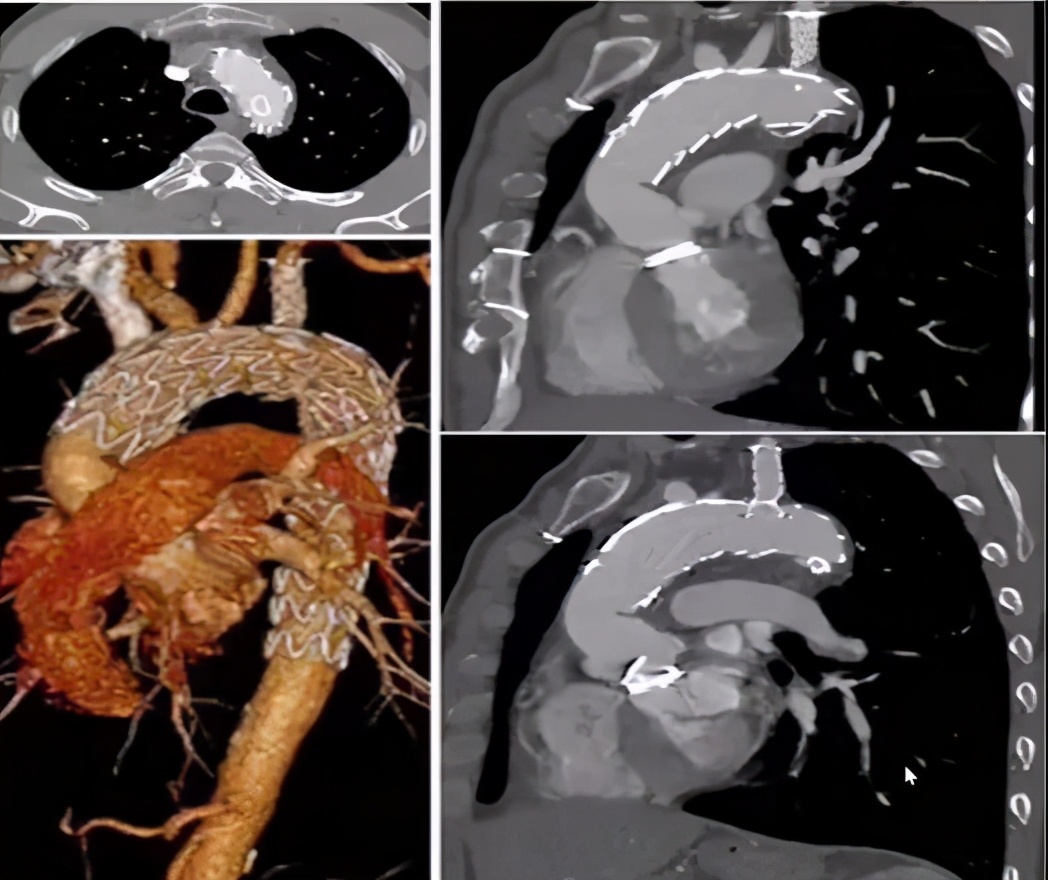

病例2(男性,66岁)

主诉:急性胸背痛1天余。

既往史:高血压。

手术史:5年前因Debakey Ⅱ型夹层行升主动脉置换术。

查体及实验室检查:血肌酐196 umol/L。

心脏彩超:(-)。

手术关注点:弓部动脉瘤原位开窗操作难度大,术中存在较大风险;而如果使用烟囱支架,则内漏风险大。所以,决定行预开窗+体外缝制内分支,增加重建弓上分支成功率,降低术中缺血风险、内漏风险。

手术方法:弓上三分支预开窗+内分支+主动脉腔内修复术。

手术步骤:弓上分支体外预开窗+内分支缝合;释放远端限制支架+近端主体支架;弓上分支支架植入。

病例3(男性,70岁)

主诉:发现主动脉弓部瘤1天。

手术史:16年前因“升主动脉瘤+AI(重度)”行Bentall手术;6月前行白内障手术。

查体及实验室检查:无特殊。

手术关注点:病变部位邻近LCCA,单纯覆盖LSA锚定区不足。IA、LCCA共干,如何重建?避免远期裸支架损失升主动脉壁的风险。

手术方法:IA、LCCA预开窗+LSA原位开窗+主动脉腔内修复术(锚定于升主动脉人工血管内)。

手术步骤:无名动脉、左颈总动脉体外预开窗;释放远端限制支架+近端主体支架;LSA原位开窗+支架植入。